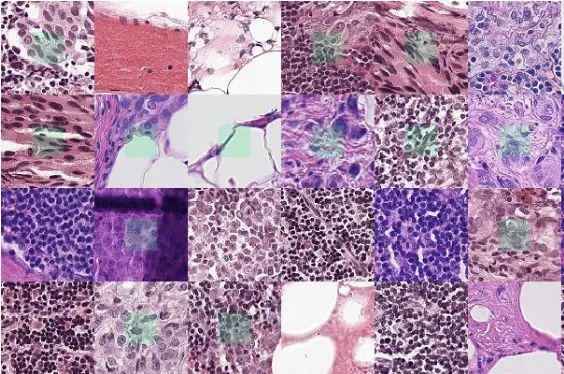

肿瘤数据集

数据集链接:http://m6z.cn/5zCyGj

这一数据集是通过仔细注释几名患有不同器官肿瘤并在多家医院被诊断出的患者的组织图像获得的。该数据集是通过从TCGA存档下载以 40 倍放大倍率捕获的 H&E 染色组织图像创建的。H&E 染色是增强组织切片对比度的常规方案,通常用于肿瘤评估(分级、分期等)。考虑到多个器官和患者的细胞核外观的多样性,以及多家医院采用的丰富染色方案,训练数据集将能够开发出开箱即用的稳健且可推广的细胞核分割技术。